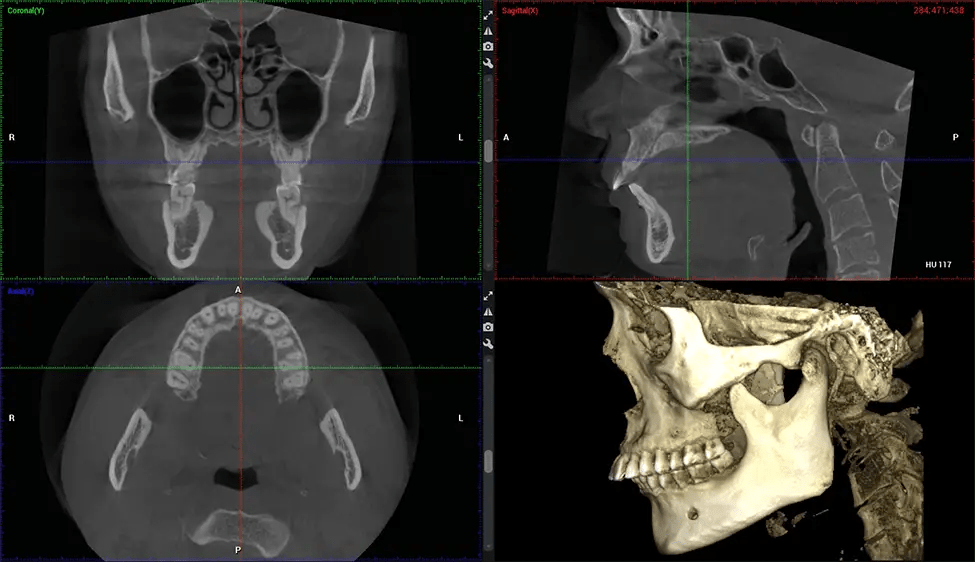

Planmeca Viso G7 CBCT ( Cone Beam CT Scan ) is designed to surpass the demands of industry leaders, specialists, and large institutions. It’s has a large ø25×30 cm sensor with four built-in cameras. It can capture unlimited volume sizes from a ø3×3 cm to a ø30x30cm volume capturing the skullcap through C7 on the cervical spine. The Planmeca Viso G7 offers the industry’s largest single volume scan of ø30×19 cm. It’s poised to handle advanced imaging modalities such as Planmeca ProFace® and Planmeca 4D™ Jaw Motion technology. The occipital head support allows an unimpeded view of facial tissue.

Planmeca is the only manufacturer clinically proven to dramatically reduce patient radiation without sacrificing image quality. Planmeca Ultra Low Dose™ achieves an average reduction in dose of 77% without a statistical reduction in image quality allowing doctors to incorporate 3D imaging into routine protocols with effective patient radiation often lower than 2D intraoral imaging. This increases patient care, allows doctors to diagnose more dentistry, and often earlier in disease progression, than with 2D imaging alone.

Our patented SCARA technology enables doctors to capture True Extraoral Bitewings that are as accurate at detecting caries as a 2D bitewing series, but with half the radiation dose. With our bitewings, doctors can view the apices of teeth on both jaws providing a more comprehensive view of the patients’ anatomy.